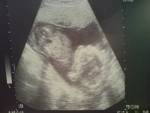

17+3 18. SSW Datum 19.05.2008 18. SSW